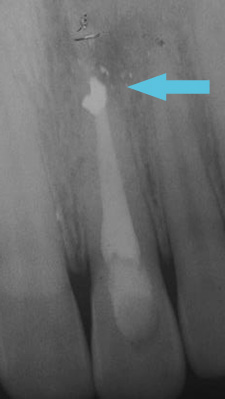

בשיניים שיש בהם תהליך זיהומי בחוד השורש, מבצעים טיפול שורש. אם עדיין קיים זיהום, ניתן לבצע חידוש טיפול שורש. במקרים שבהם לא ניתן לבצע חידוש טיפול שורש (למשל שן עם כתר) או שחידוש טיפול שורש עדיין לא פתר את הבעיה, ניתן לבצע טיפול אפיסקטומי, שהוא בעצם ניתוח באזור חוד השורש, שבמהלכו מסלקים תהליך זיהומי ומבצעים אטימה נוספת מאזור חוד השורש.

דוגמה: תהליך זיהומי שהתרחש בשן בעקבות חבלה (נפילה). השן עברה טיפול שורש וחידוש טיפול שורש, אך עדיין היה זיהום נרחב.

תהליך זיהום בשן אפיסקטומי

ריפוי מלא הושג חצי שנה לאחר אפיסקטומי.